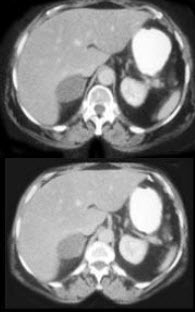

7、单项选择题

根据所提供的图像,最可能的诊断是()

A.急性肾盂肾炎

B.肾癌

C.黄色肉芽肿性肾盂肾炎

D.肾梗死

E.肾血管平滑肌脂肪瘤

点击查看答案